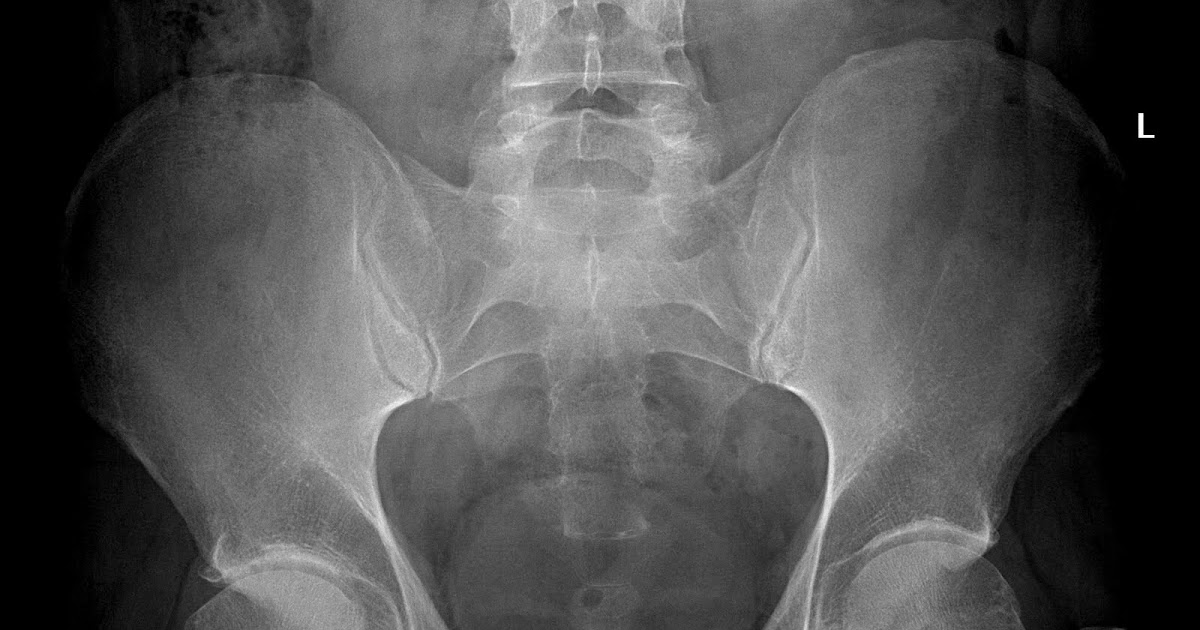

Cam-Type Fai Radiology . Cam type fai is predominantly the result of an. Femoroacetabular impingement (fai) is the abnormal contact between the femur and acetabulum which may lead to labral damage, various degrees of chondral injury and progressive. Section of anteroposterior pelvic radiograph shows regular acetabular configuration with acetabular fossa lying lateral to ilioischial line. Pelvic radiography with dedicated hip projections is the basis of the diagnostic workup of patients with suspected fai to assess arthritic. Arrows show herniation pit caused by cam type of femoroacetabular impingement. Iil = ilioischial line, aw = anterior wall, pw = posterior wall, f = fossa. Learn about the causes, symptoms, diagnosis and treatment of fai, a condition that affects the hip joint and causes pain and limited motion. Find out how to identify cam, pincer and mixed.